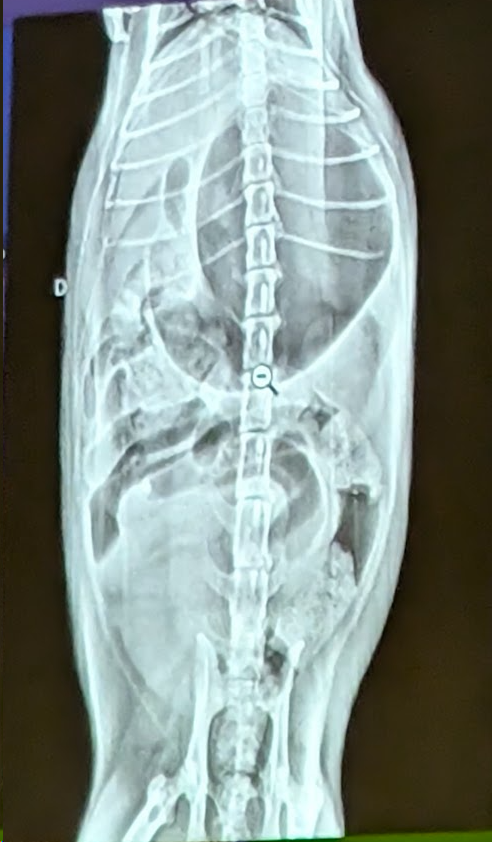

Preguna 1 - Multiple respuesta

- Se trata de un abdomen de gato

- Obstrucción intestinal

- Presenta una dilatación gastrica sin torsión (ya que el fundus y piloro gastrico están en su sitio).

Preguna 2 - Multiple respuesta

- Se trata de un abdomen de perro

- Dilatacion gastrica

- Cuerpo extraño en el estomago (Linea radiopaca en el piloro)

- Eje gastrico alterado.

- Cumple dos criterios de hepatomegalia. (El higado ocupa mas parte, avanzando mas costillas, desplaza al estomago)